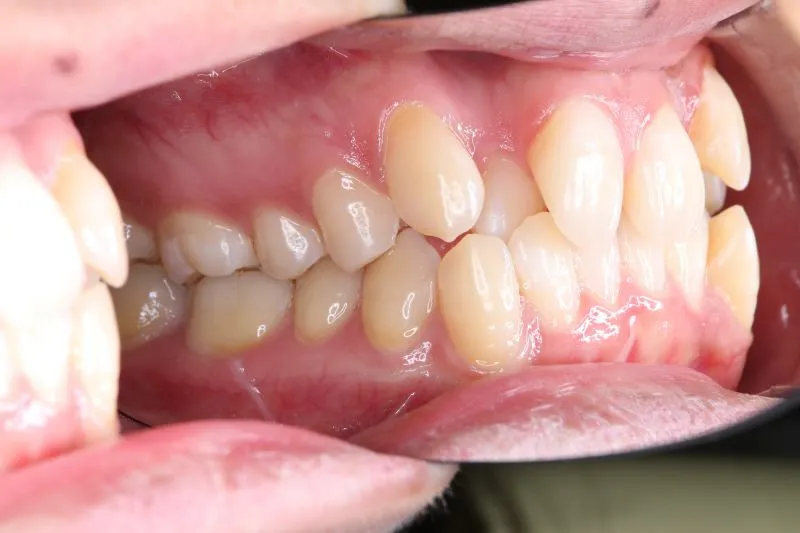

• 初診

初診時年齢 19~29歳 (女性) 主訴 ガタガタ・交叉咬合が気になる

診断名 叢生・交叉咬合 装置名

ガタガタ・八重歯を主訴に来院された患者様です。

頬杖をする癖がおありでした。

初診